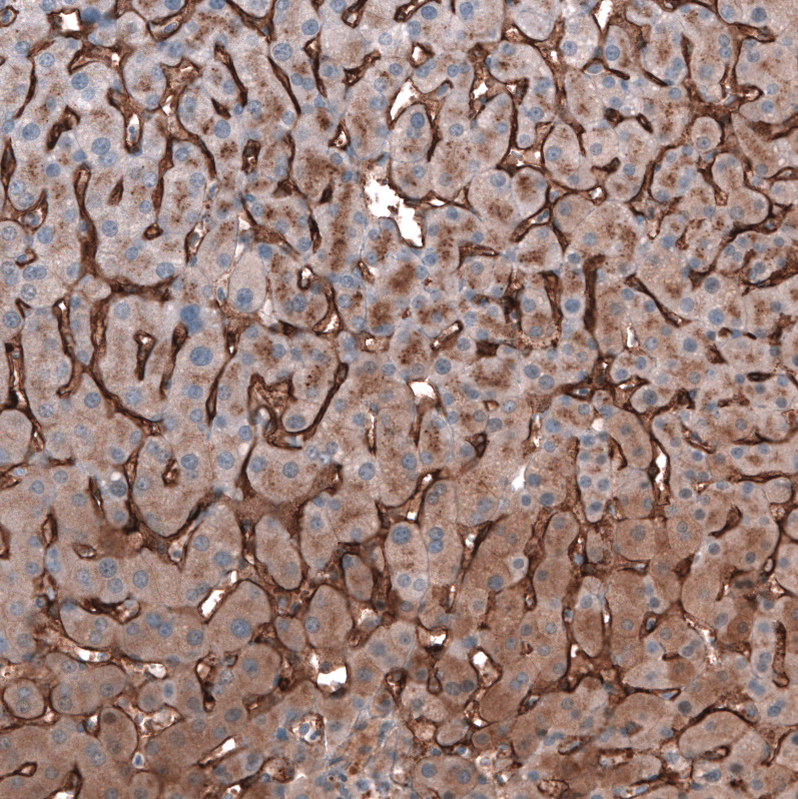

Immunohistochemical staining of human liver shows strong membranous positivity in hepatocytes.